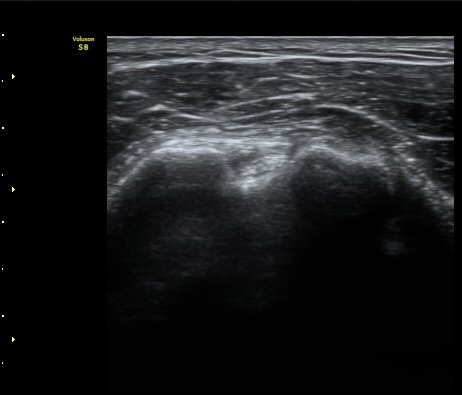

ÁÖ»ç ÈíÀΰú Á¡¾×³¶³» ÁÖ»çÄ¡·á(÷ºÎ ÆÄÀÏ) 1ÀÏ ÈÄ ½ÃÇàÇÑ °Ë»ç¿¡¼­ Á¡¾×³¶ÀÇ ºÎÁ¾ ¹× ¼®È¸ÀÇ

Á¦°Å°¡ °üÂû µÊ(±×¸² 6, 7).